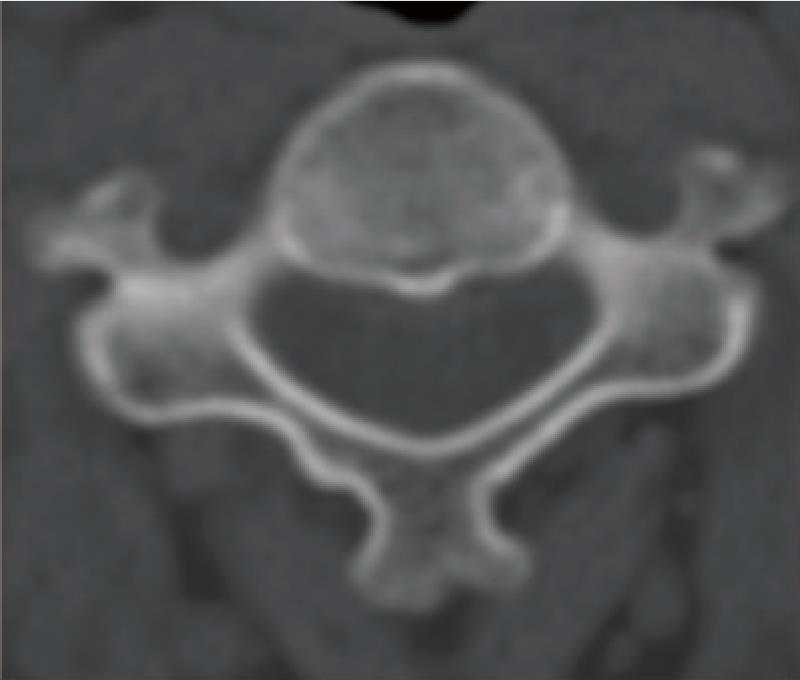

病例4: 颈椎骨性斜颈矫形术

骨性斜颈,术前X线和CT示颈椎半椎体合并椎体分隔不全畸形

颈椎前路后路联合截骨矫形术,随访X线和CT示矫形效果满意。